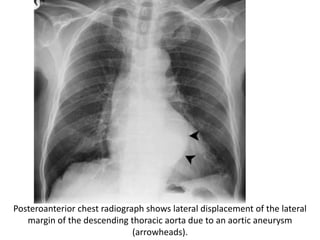

Posteroanterior chest radiograph shows lateral displacement of the lateral

margin of the descending thoracic aorta due to an aortic aneurysm

(arrowheads).

Posteroanterior chest radiographshows lateral displacement of the lateral margin of the descending thoracic aorta due to an aortic aneurysm (arrowheads).